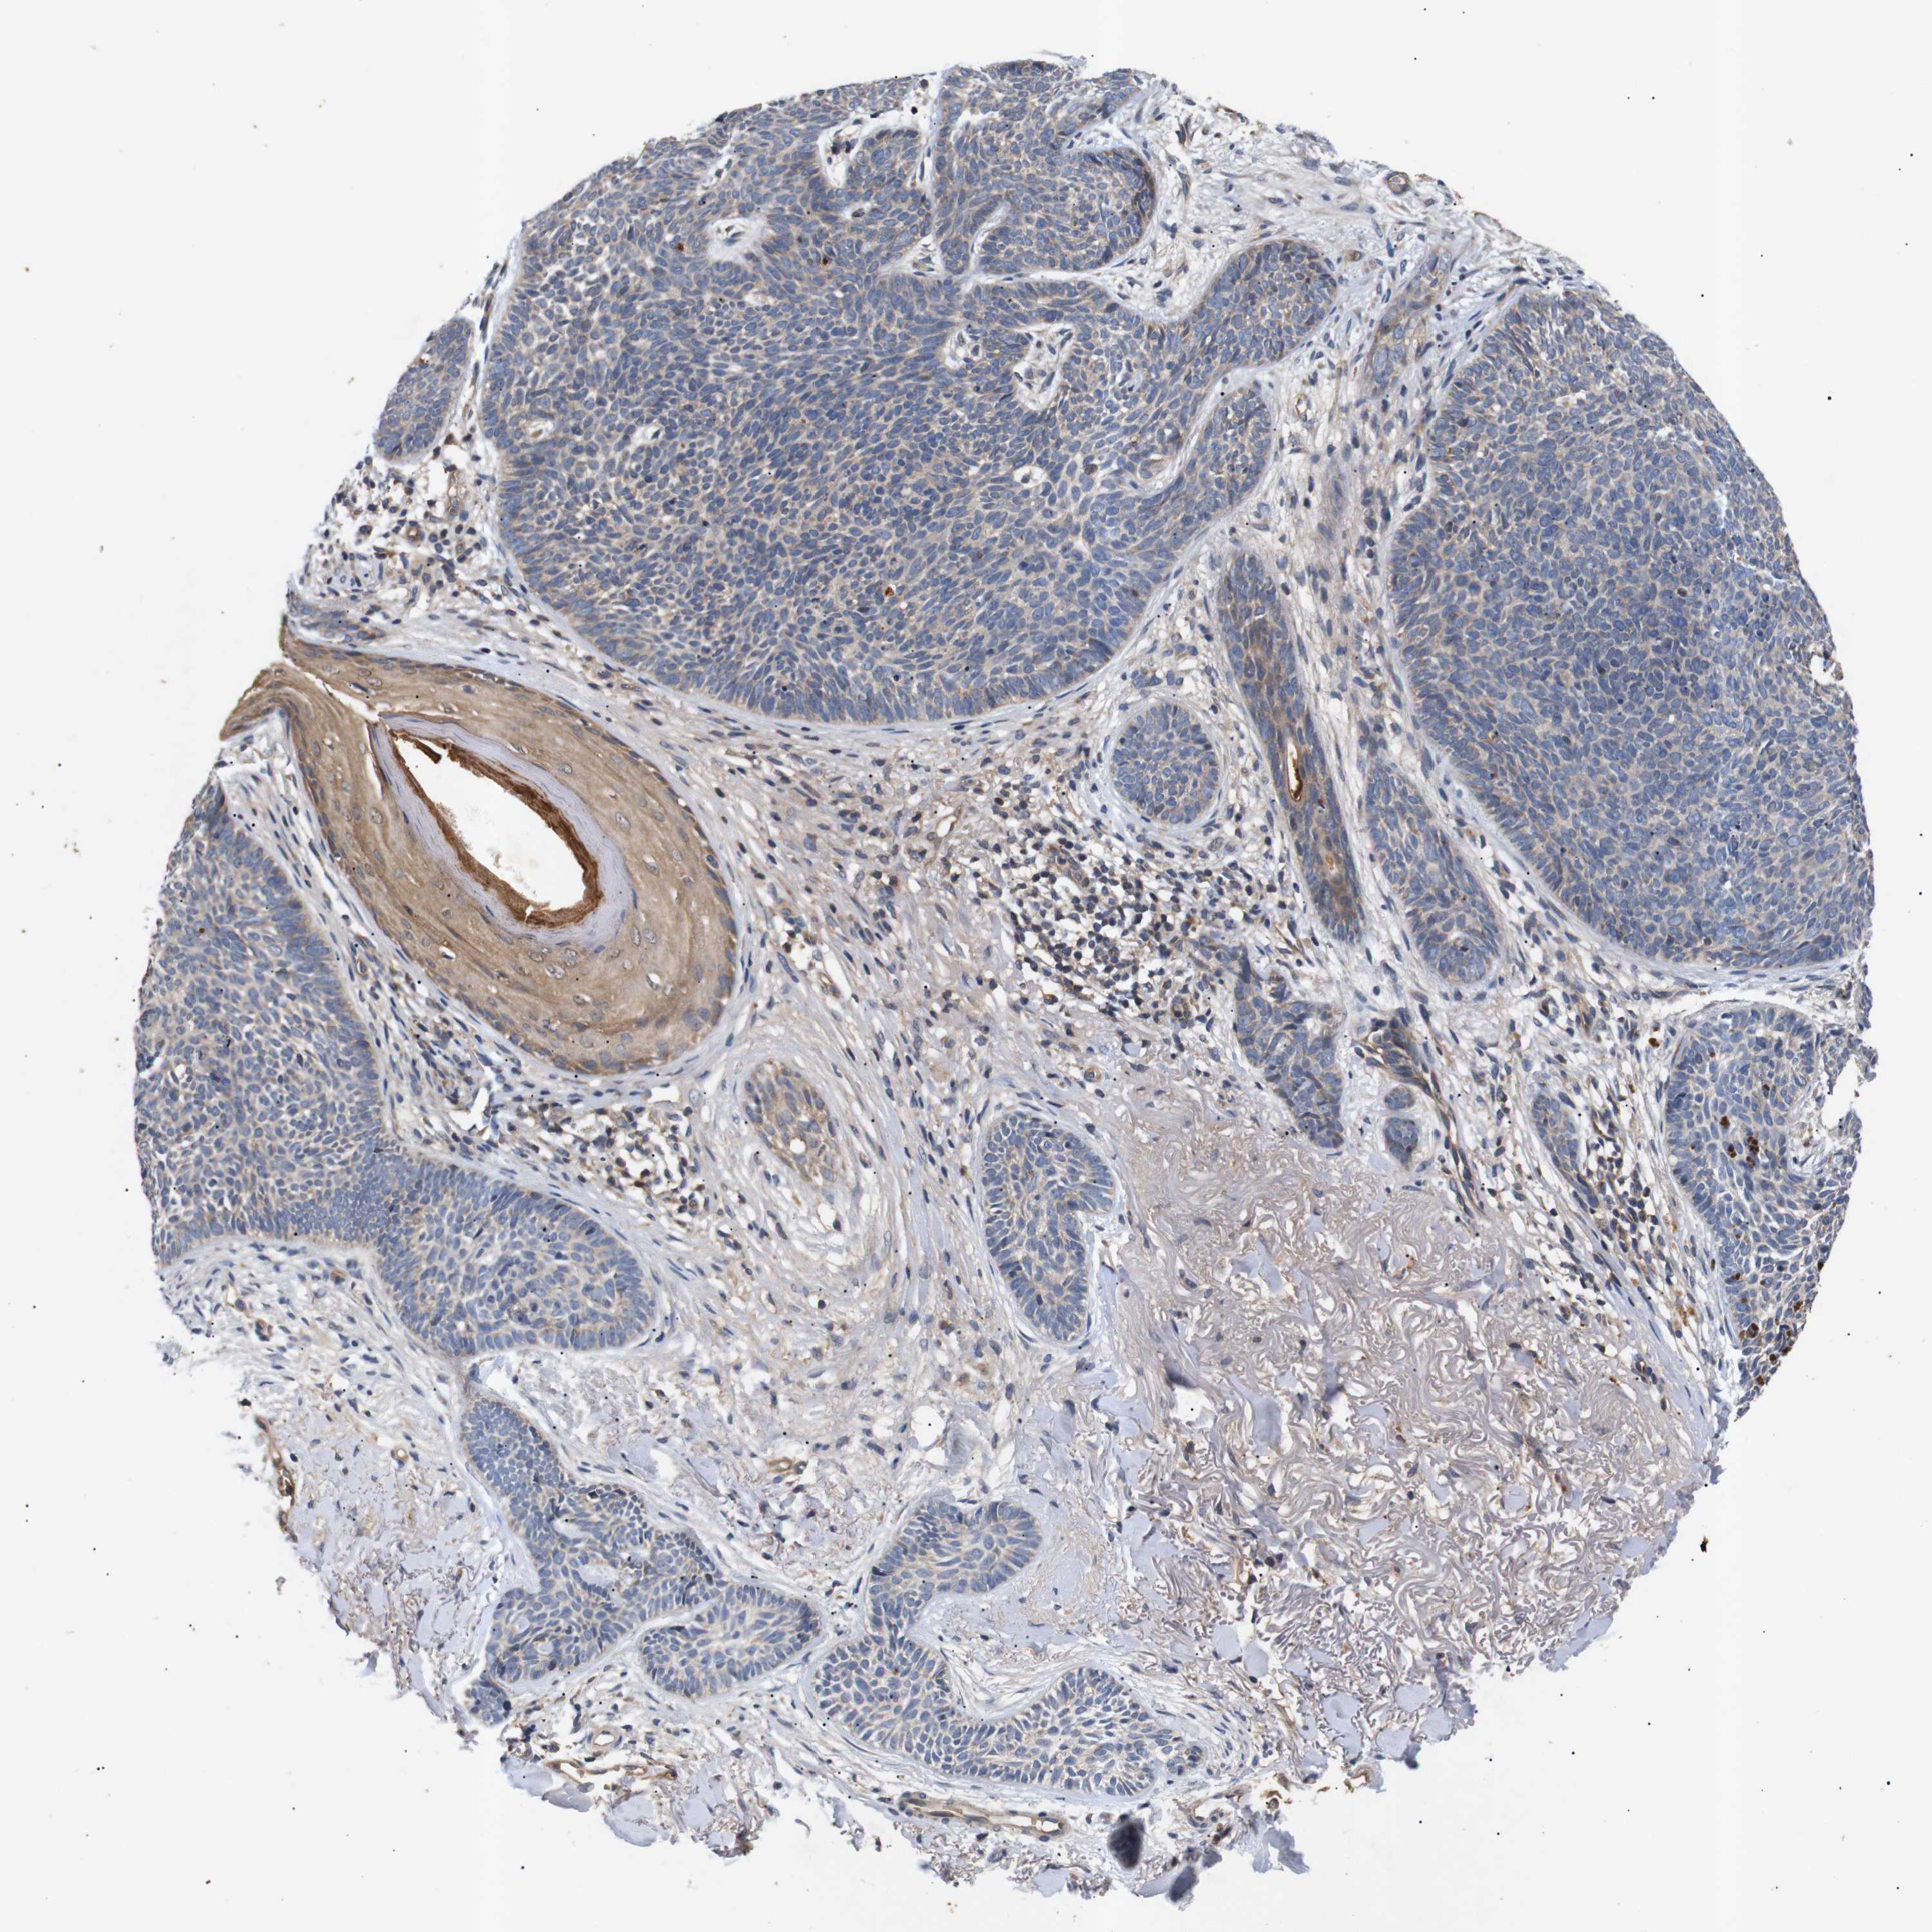

SKIN CANCER - Protein expressioni

A mouse-over function shows sample information and annotation data. Click on an image to view it in a full screen mode. Samples can be filtered based on level of antibody staining by selecting one or several of the following categories: high, medium, low and not detected. The assay and annotation is described here.

Each image is clickable and will lead to virtual microscopy that enables deeper exploration of all samples and also displays staining intensity scores, fraction scores and subcellular localization as well as patient and tissue information for each sample.

Antibody HPA015257

Squamous cell carcinoma in situ, NOS

Squamous cell carcinoma, NOS

Squamous cell carcinoma, metastatic, NOS

Basal cell carcinoma

Adnexal tumor, benign